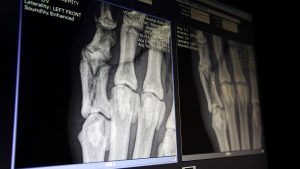

بقلم: يورونيوز نشرت في 26/09/2025 – 7:00 GMT+2 اعلان في دراسة نُشرت حديثًا في مجلة “ACS Nano”، طوّر باحثون زجاجًا حيويًّا نشطًا قابلًا للطباعة ثلاثية الأبعاد، أظهر فعالية لافتة في دعم تكوين العظام، متفوقًا في الأداء على الزجاج العادي والبدائل العظمية المتوفرة تجاريًّا، وفق تجارب أُجريت على أرانب. خصائص مشتركة بين…